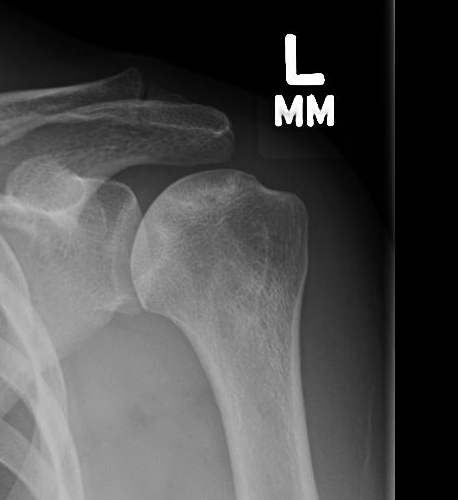

Classification / Cruess modification of Ficat-Arlet

Stage I - pre-xray change / diagnosed on MRI

Stage II - sphericity maintained / sclerotic changes in superior central head / crescent sign

Stage III - mild flattening articular surface

Stage IV - significant humeral collapse with loss integrity joint surface

Stage V - degeneration extends to involve glenoid